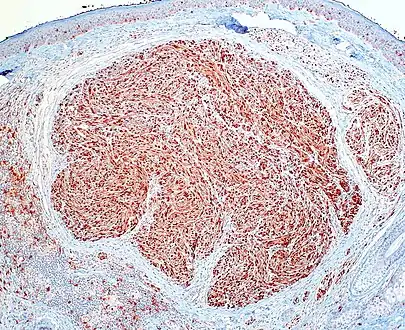

Palisaded and Encapsulated Neuroma

Skin tumors(palisaded encapsulated neuroma)